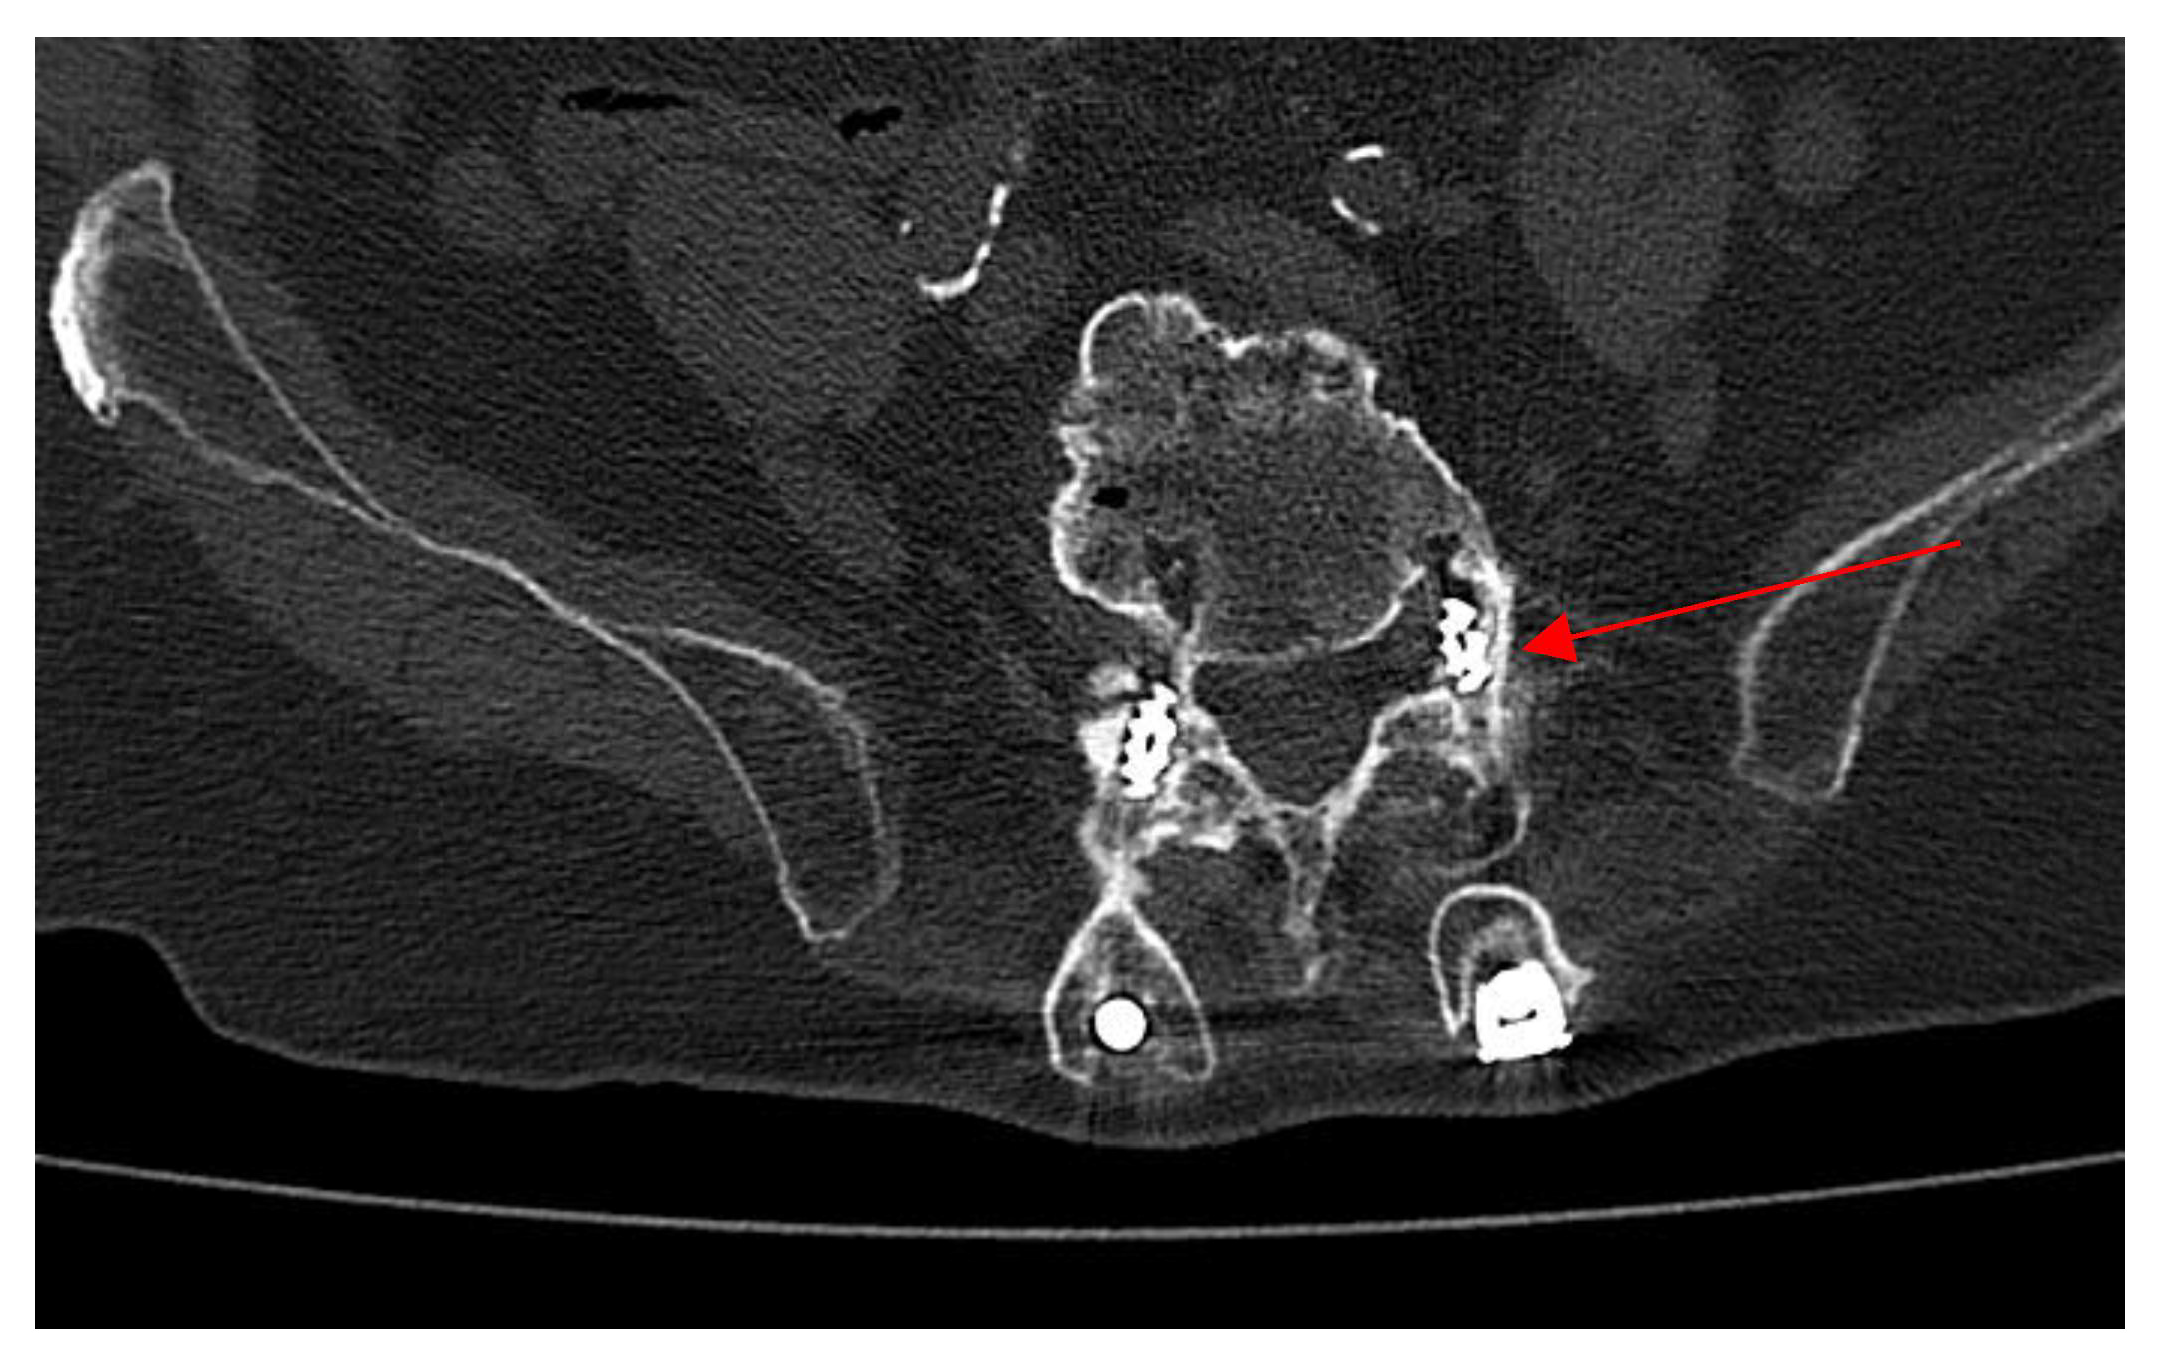

2.3. Admission to Infectious Diseases Unit

2.4. Neurosurgery Evaluation